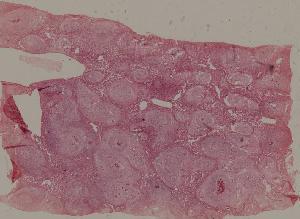

76. Acute pyelonephritis